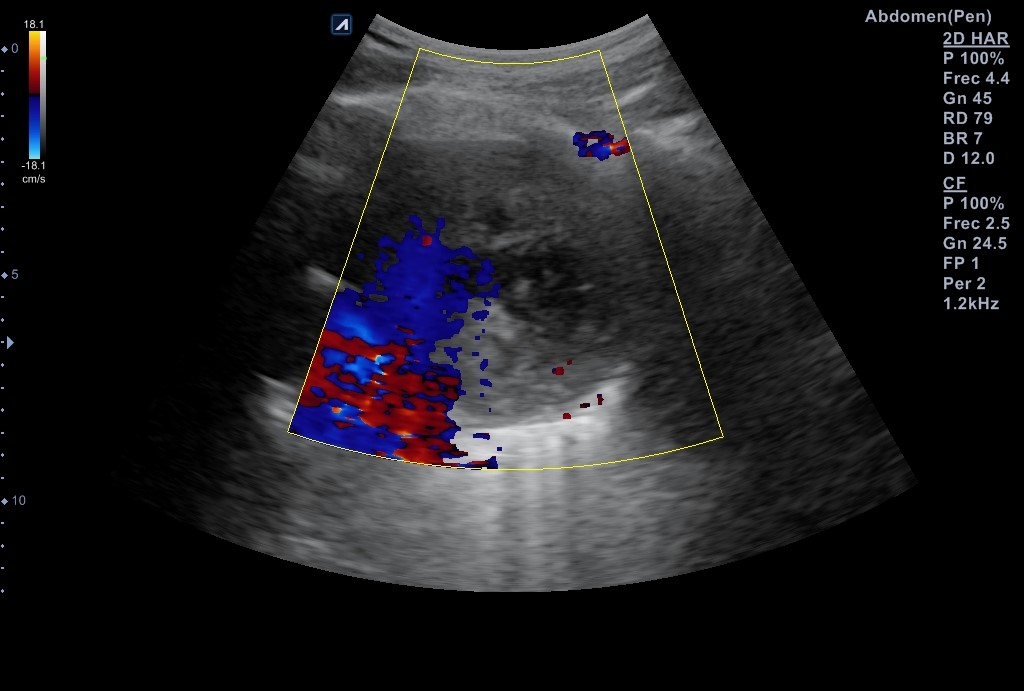

Se realiza ecografía pulmonar donde se identifica una masa anterior en el vértice del pulmón derecho, de aspecto sólido con centro necrótico de unos 7-8 cm de diámetro en anteroposterior y transversal, sin poder precisar diámetro longitudinal por interposición de costillas, clavícula y esternón.

Masa en mediastino anterior izquierdo. Diagnóstico diferencial: linfoma vs timoma vs neoplasia pulmonar. Se contacta con Medicina Interna para estudio urgente, donde le solicitan un TC cuello-tórax con contraste IV (resultados: masa en vértice medial pulmón izquierdo, de contorno bien definido y abundante necrosis) Mide 12,5 x 5,3 x 7,5 cm.